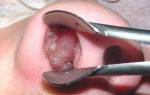

- Осмотра задней части носоглотки (проводится с использованием зеркала через рот);

- Эндоскопического осмотра (проводится с применением эндоскопа – микрокамеры, при обязательной анестезии);

При проведении пальцевого исследования не стесняйтесь задавать врачу вопросы о характере поражений. В случае воспалительного процесса наблюдаются следующие особенности:

- Присутствие гнойного налета на аденоидах;

- Гладкая и однородная структура миндалин;

- Бледный, синюшный или ярко-красный оттенок.